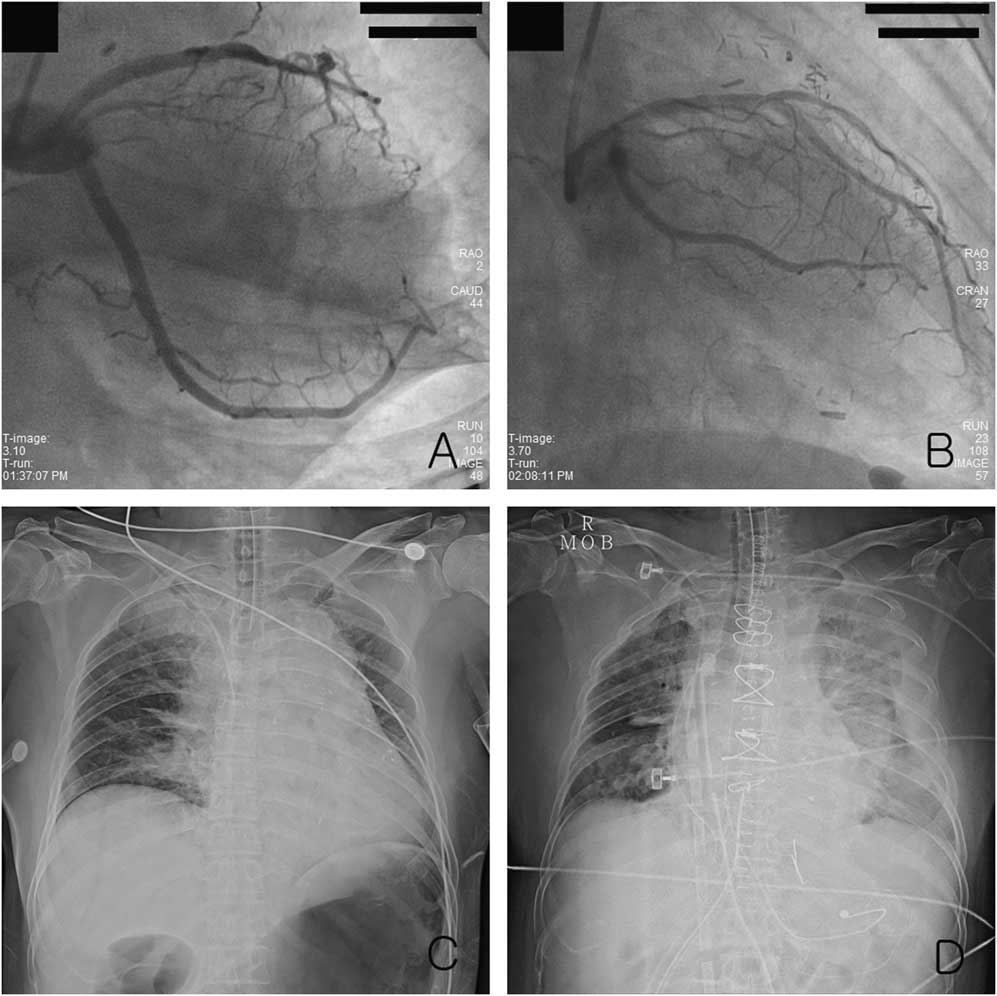

A 60-year-old woman with hypertension and vasospastic angina who had undergone coronary artery bypass grafting in 2001 was admitted to a local clinic for fiberoptic gastroscopy. Cardiac arrest occurred shortly after insertion of the gastroscope, and CPR was begun by a physician. The initial rhythm was asystole at the time of arrival of the paramedics. Twenty-eight minutes elapsed between the time of the arrest and arrival at the emergency department (ED). The vital signs on arrival at ED were blood pressure of 85/70 mm Hg, heart rate of 131 beats/min. She was intubated, was comatose, and her body temperature was 35.4°C. Cardiac arrest with PEA recurred several times. ECPR (Capiox Emergency Bypass System, Terumo Inc., Tokyo, Japan) was begun 82 minutes after ED arrival due to recurrent arrest, despite the use of inotropic agents and vasopressors. Coronary angiography and balloon angioplasty were performed at the ostial occlusion lesion of the obtuse marginal artery (Figure 1, A and B). Several medications were administered: 300 mg aspirin, 600 mg clopidogrel, and 6000 IU heparin. The patient showed ventricular fibrillation (VF) and PEA after angioplasty, and extracorporeal cardiopulmonary membrane oxygenation (ECMO) was maintained. After coronary angiography, echocardiography revealed cardiac tamponade, and pericardiocentesis removed 250 mL of nonclotting blood. As refractory shock persisted in spite of pericardiocentesis, open thoracotomy was performed 4 hours after ED arrival (see Figure 1, C and D). A large pericardial hematoma and enlarged edematous heart were identified, and a 2- to 3-cm vertical laceration of the left ventricle on the lateral free wall was repaired. A second open thoracotomy was performed due to low cardiac output and a massive left hemothorax on the second hospital day (HD). The sternum was left open because of the enlarged, edematous heart, and closure of the sternum and weaning from ECMO occurred on HD 6. The patient had a clear sensorium after discontinuing sedatives on HD 6 but developed left lower extremity motor weakness on HD 17. Diffusion-weighted magnetic resonance imaging revealed an embolic infarction in the right upper basal ganglia and the genu of corpus callosum. The patient was ultimately transferred to a rehabilitation centre for stroke rehabilitation with a Glasgow Coma Scale (GCS) score of 15 on transfer.

Figure 1 The right anterior oblique view of coronary angiography: A) showed the occlusion of the obtuse marginal artery and B) revealed that coronary arterial flow after balloon angioplasty was improved. Chest radiography showed C) the wide mediastinum before thoracotomy and D) pulmonary edema with pleural effusion after thoracotomy.